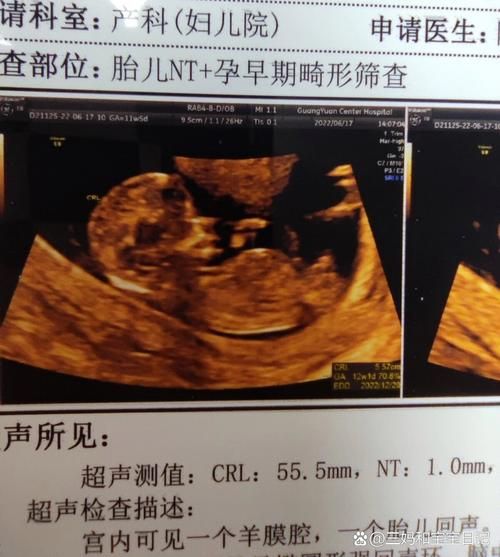

拿到四维报告,看到“胎儿鼻骨缺失”五个字,多数准爸妈瞬间大脑空白。它并不等于孩子一定畸形,而是提示染色体异常风险升高,**最常见关联的是21三体(唐氏综合征)**。 医生通常会建议无创DNA或羊水穿刺进一步排查,**影像上没拍到鼻骨,也可能只是体位遮挡或骨化延迟**。

- 第一步:确认孕周——鼻骨在11周开始骨化,14周前未显示属正常。